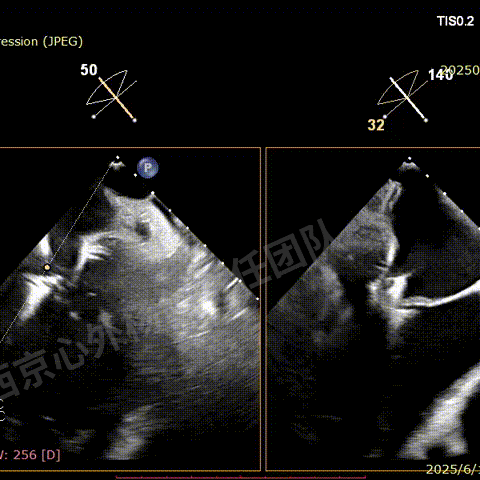

第二枚XT关闭后评估,trace

二尖瓣平均跨瓣压差1mmHg

释放后评估,反流降至1+,组织桥稳定

SGC撤回右房后,观察到有右向左的反流,血氧饱和度下降

行房间隔封堵

M-TEER术后三尖瓣反流减轻